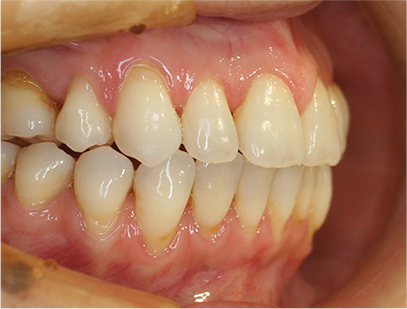

治療後

• 右側

治療前の写真と治療後の写真を比べると口元が治療前は下唇が出ていて、鼻の下が凹んでいました。上顎の前歯のデコボコも綺麗に並びました。また、上下の前歯は開咬が治りしっかりと咬み合ってます。

治療期間は患者様の協力が大変に良かったために2年半とさほど長くはありませんでした。

• 口元が綺麗になった事、上下の前歯が咬み合った事、八重歯が改善された事。